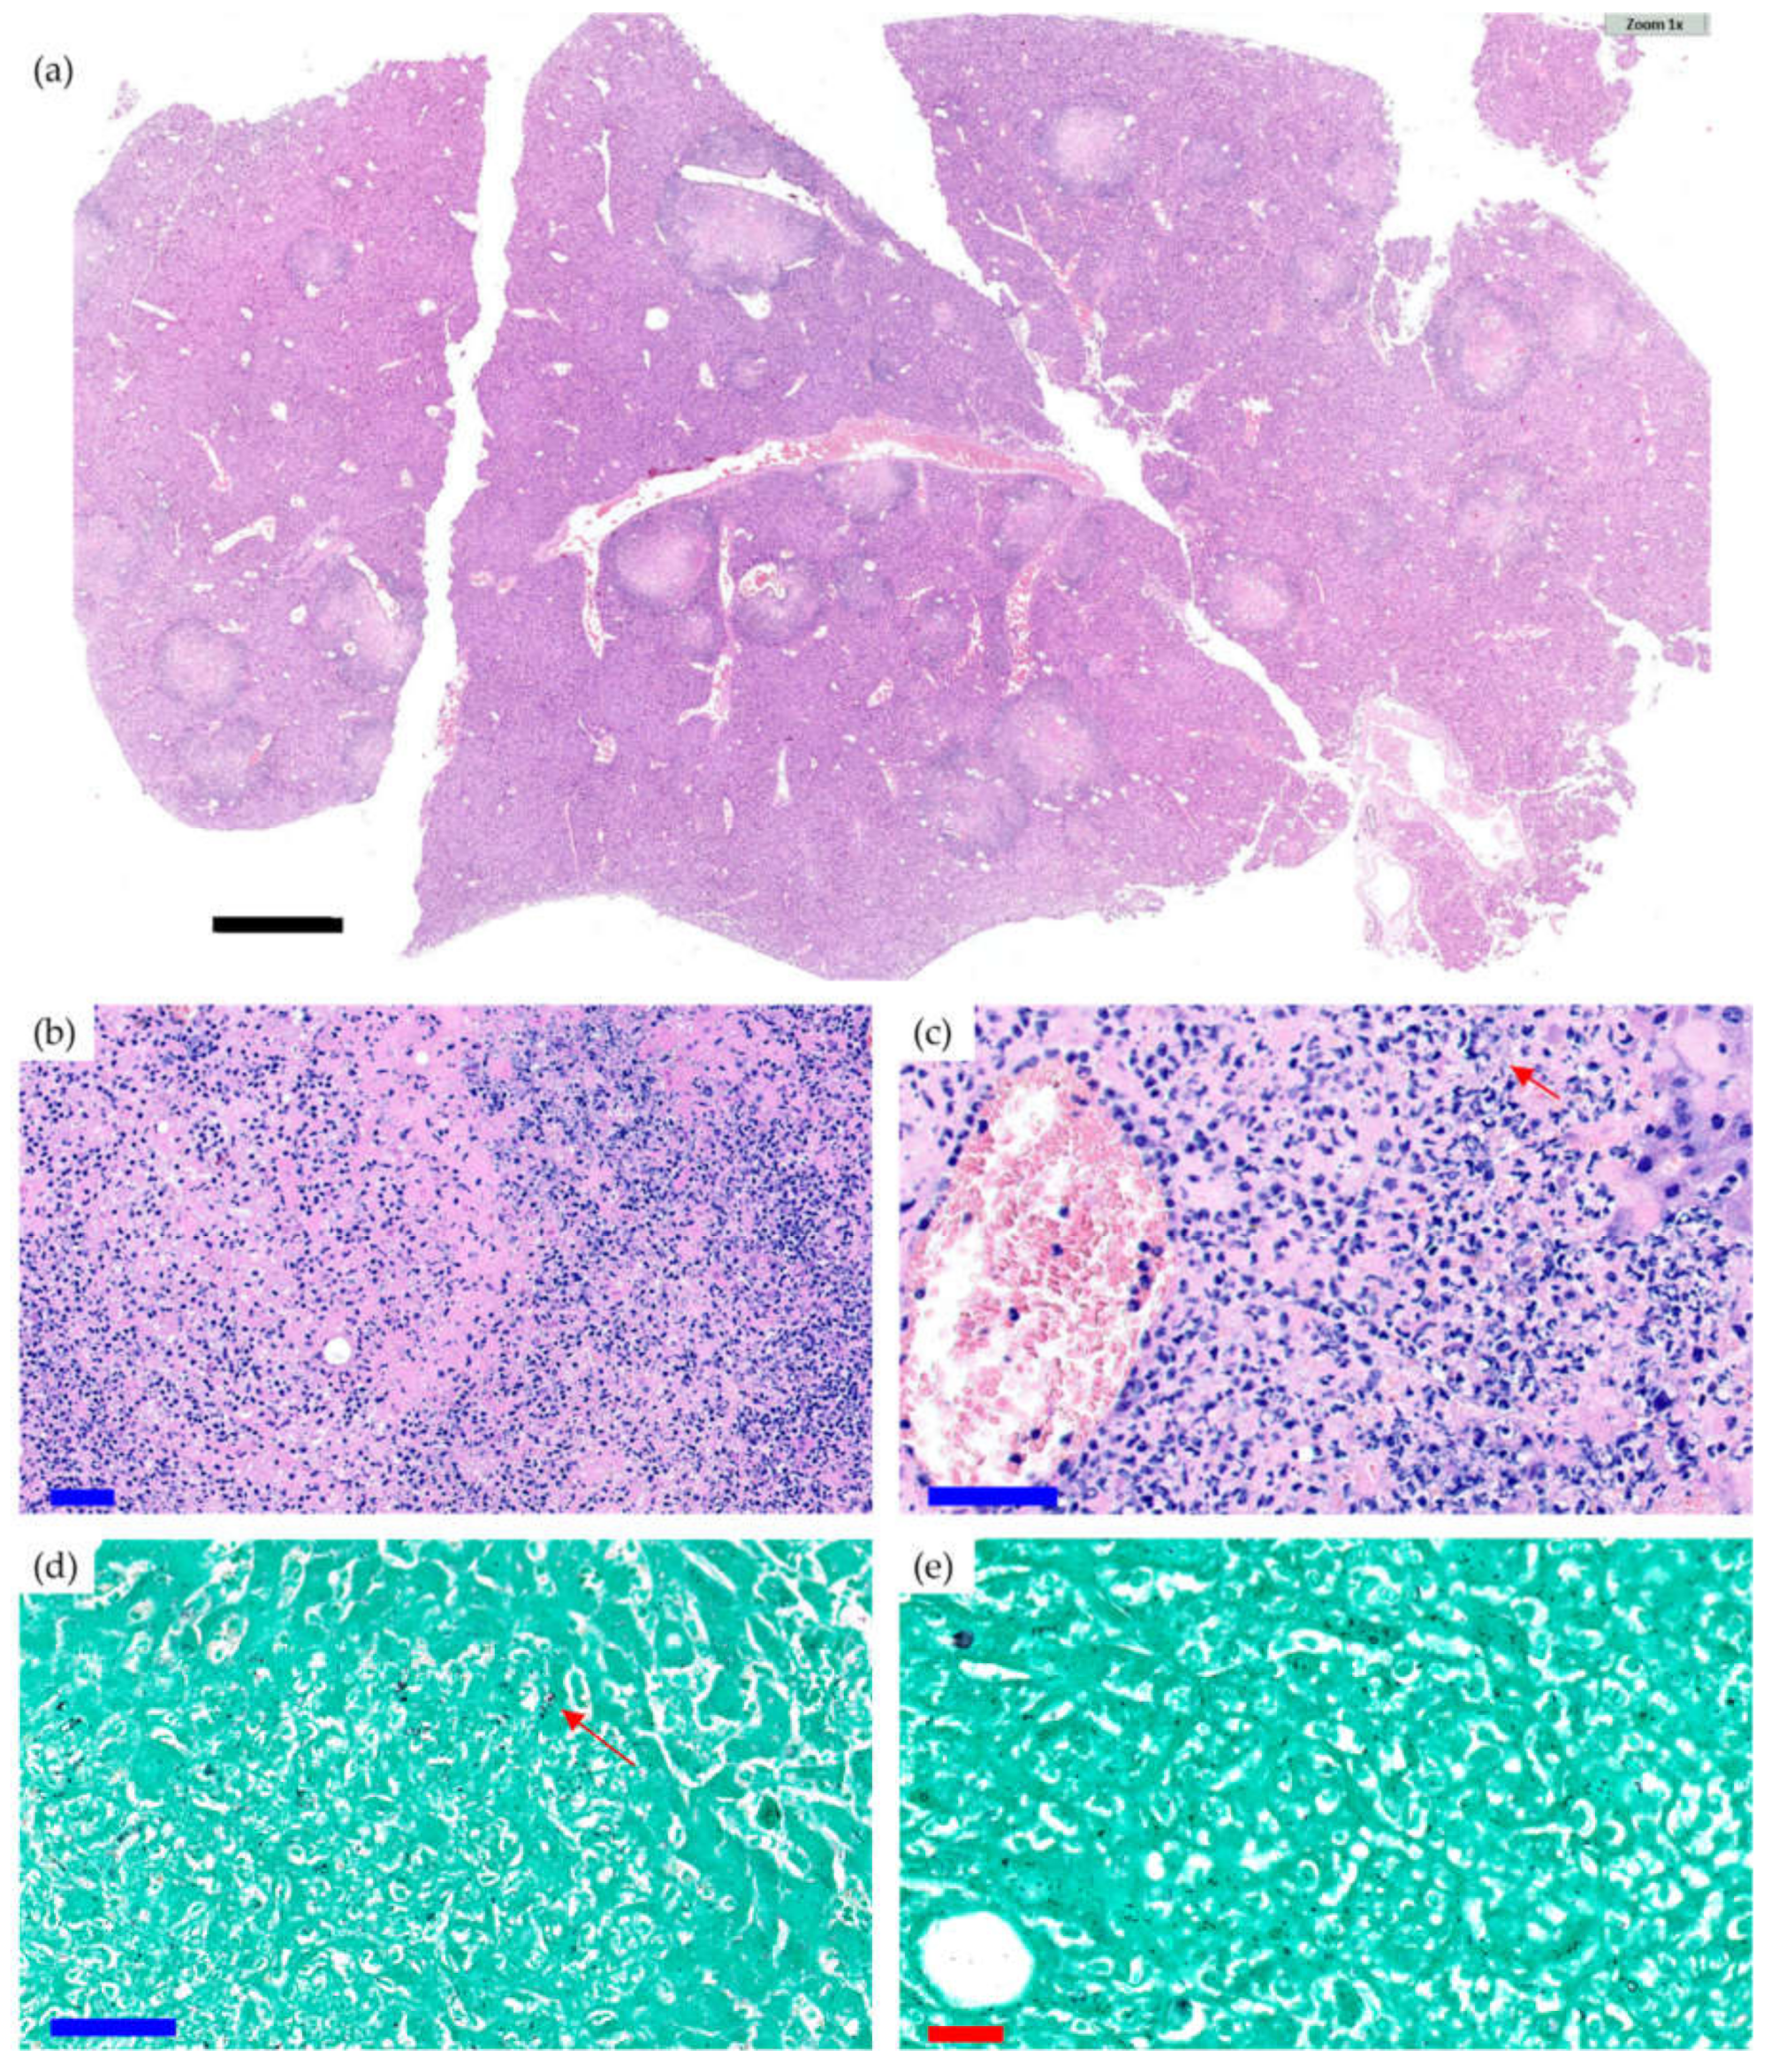

2.2. Microbiological and Pathological Results

2.3. Microcomputed Tomography and Bone Histology

- Acute osteomyelitis was defined as bone tissue evidencing moderate-to-high–intensity polymorphonuclear (PMN) inflammatory response with tissue necrosis phenomena and trapping of trabecular bone remains;

- Chronic osteomyelitis was defined as bone tissue that presents a variable inflammatory reaction, partially consisting of a PMN response, but mainly of plasma cells and lymphocytes;

- PJI was diagnosed when any type of osteomyelitis and the presence of yeast were evidenced.